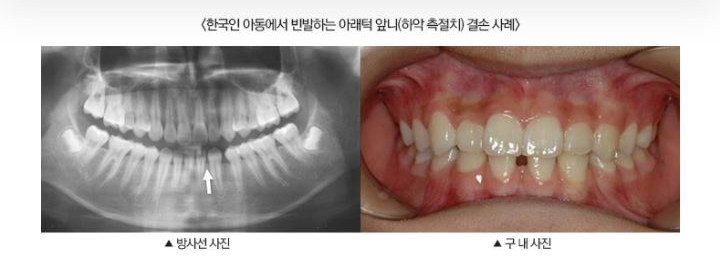

일본 연구진, '치아 자라게 하는 약’ 사람 대상 임상 계획···임플란트 대안 될까?

일본 연구진이 치아를 자라게 하는 약을 개발해 올해 말 실용화를 위한 임상시험을 시작한다. 3일 일본 교도통신에 따르면 일본 기타노병원과 제약벤처인 ‘트레젬 바이오파마’는 이날 태어나면서 영구치가 적은 ‘선천성 무치증’ 환자의 치아를 자라하게 하는 약을 최근 개발, 오는 9월쯤 인체 안전성을 확인하기 위해 사람을 대상으